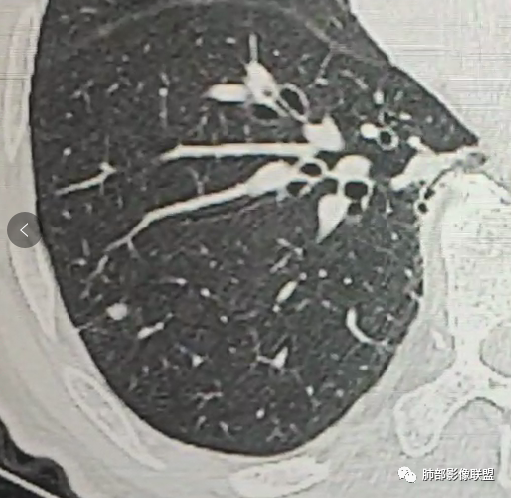

病史时间:2018年8月12日确诊左肺上叶肺腺ca射频消融,2020年1月13日左肺下叶未见结节,2021年3月14日新发双肺下叶(视频图)见4枚实性小结节,边清,目测低强化,胸膜下的结节(3个)与胸膜粘连的特点,无收缩力,前后1年余倍增明显结节,多发,支持炎性肉芽肿结节,隐球菌荚膜抗原检查,其次与转移鉴别,非随机,位置仅双肺下叶,可能性小,建议左肺下叶后基底结节定位穿刺活检!

现实工作中万万不能排除转移,但是这几个结节位于左肺下叶背段,周围可见小结节卫星灶,部分胸膜下结节可见胸膜凹陷征,常规考虑原发肿瘤或肉芽肿病变,一个肺区域如此多结节,肉芽肿病变靠前考虑。

2、影像特点:左肺上叶尖后段病灶结合病史考虑消融术后改变,双肺下叶胸膜下可见多发大小不等的实性结节,周围似乎有晕,边缘平直为主,未见深分叶,部分可见邻近胸膜牵拉,张力不高,增强后呈轻中度强化。